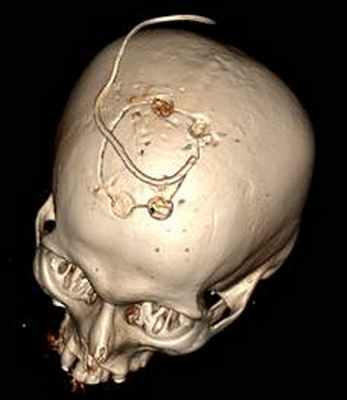

КТ головного мозга (30.10.2015): состояние после КПТЧ и микрохирургического удаления объемного образования головного мозга. Постоперационная киста, пневмоцефалия.